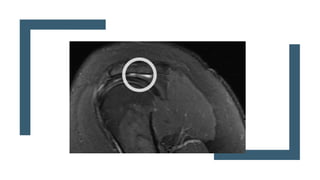

■ Resonancia magnética

Imagenes en T2

Cortes coronales

Tendones mantienen una señal baja

Roturas se presentar como imagenes potenciadas en T2